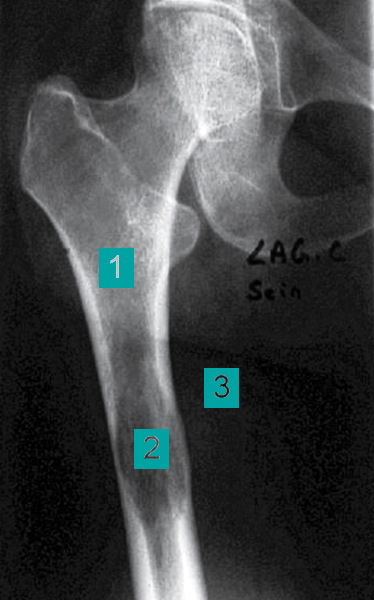

La lyse est irrégulière, mal limitée (1). Elle contient quelques ossifications qui sont des résidus osseux partiellement détruits (2). Les corticales sont amincies, de façon irrégulière avec quelques effractions (3). Cet aspect radiologique est agressif, évoquant fortement une tumeur maligne.